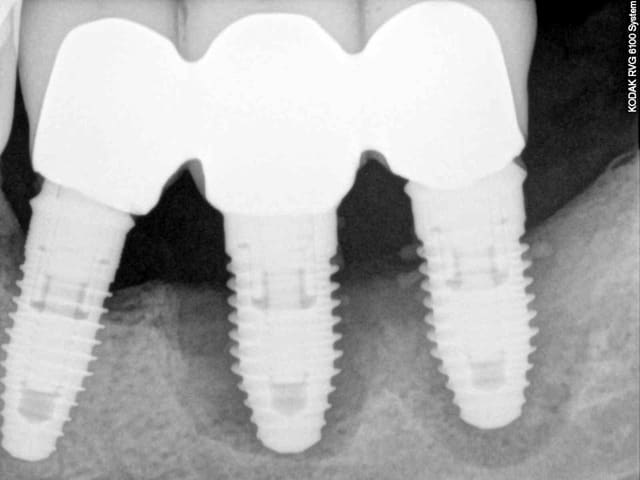

2 rétro-alvéolaire (septembre 2012)

un an après !

ça s'arrange pas, voyez plutôt..

augmentation de la perte osseuse +++